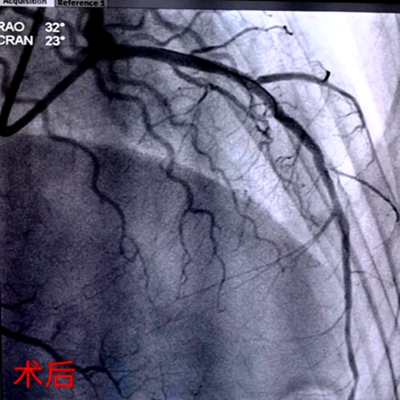

3月26日,心血管内科主任彭道地教授及范爱德副主任共同顺利为熊爷爷完成手术,冠脉造影提示:冠状动脉多支多处严重狭窄病变;其中前降支次全闭塞并钙化病变,在狭窄处植入2枚支架后血管开通。 术后,熊爷爷恢复良好,自己明显感觉心里舒服了,胸痛、胸闷等症状也消失了,晚上可以躺着睡个好觉了。